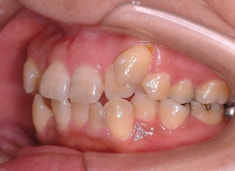

治療前